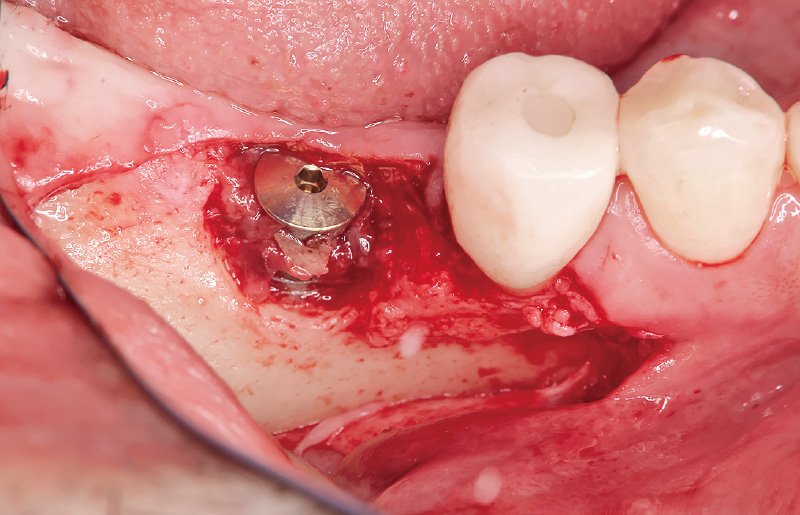

図6 骨補填材は「ボナーク」を充填する。 -

図7 テンションフリーを確認し、水平的マットレスと単純縫合を行う。 -